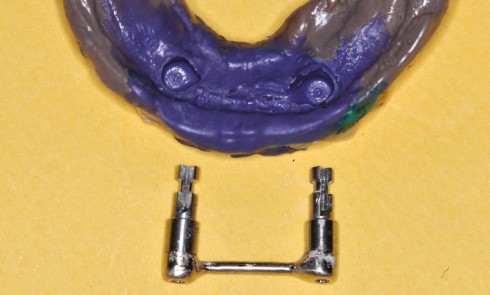

Article réservé à nos abonnés PACSI : réfections en présence d’une barre de conjonction

De nos jours, le degré de satisfaction des patients porteurs de prothèses amovibles complètes (PAC) est limité. En particulier, pour...